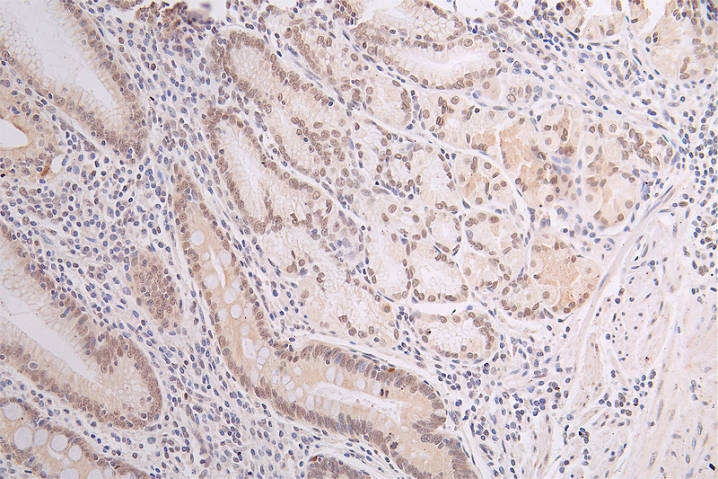

IHC image of CSB-RA796958A0HU diluted at 1:50 and staining in paraffin-embedded human gastric cancer performed on a Leica BondTM system. After dewaxing and hydration, antigen retrieval was mediated by high pressure in a citrate buffer (pH 6.0). Section was blocked with 10% normal goat serum 30min at RT. Then primary antibody (1% BSA) was incubated at 4°C overnight. The primary is detected by a Goat anti-rabbit polymer IgG labeled by HRP and visualized using 0.67% DAB.